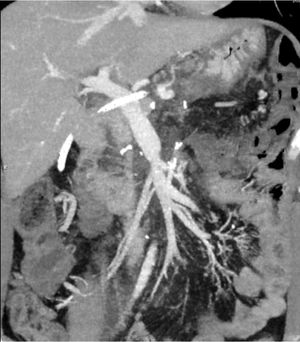

The resection of locally advanced adenocarcinoma of the pancreatic head with occlusion of the superior mesenteric vein and involvement of the splenomesenteric portal confluence (EMP) sometimes requires prolonged venous clamping with risk of intestinal ischemia. The use of intraoperative venous shunts has been published by reference groups to allow successful resection. In our centre we performed a total pancreatoduodenectomy for locally advanced pancreatic head adenocarcinoma with superior mesenteric vein occlusion (SMV) and splenomesenteric portal confluence. The use of a temporary ileo-caval shunt via a venous graft allowed resection of the tumour without repercussion on the bowel. The surgery ended with closure of the shunt, anastomosis of the graft to the portal vein and digestive reconstruction. The patient presented good tolerance to surgery and was discharged on the 7th postoperative day. The pathology report described pancreatic adenocarcinoma ypT1N0(R0) regression grade GRT2/IIa, with 0/30 affected adenopathies.

La resección de adenocarcinoma de cabeza de páncreas localmente avanzado con oclusión de la vena mesentérica superior y afectación del confluente esplenomesentéricoportal (EMP) obliga en ocasiones a un clampaje venoso prolongado con riesgo de isquemia intestinal. La utilización de shunts venosos intraoperatorios ha sido publicado por grupos de referencia para permitir la resección con éxito. En nuestro centro realizamos una duodenopancreatectomía total por adenocarcinoma de cabeza de páncreas localmente avanzado con oclusión de vena mesentérica superior (VMS) y confluente esplenomesentéricoportal. El uso de un shunt ileo-caval transitorio mediante un injerto venoso permitió la resección del tumor sin repercusión en el intestino. La cirugía finalizó con el cierre del shunt, anastomosis del injerto a la vena porta y reconstrucción digestiva. El paciente presentó buena tolerancia a la cirugía, siendo dado de alta el 7 ° día postoperatorio. El estudio anatomopatológico describió adenocarcinoma pancreático ypT1N0(R0) grado regresión GRT2/IIa, con 0/30 adenopatías afectas.